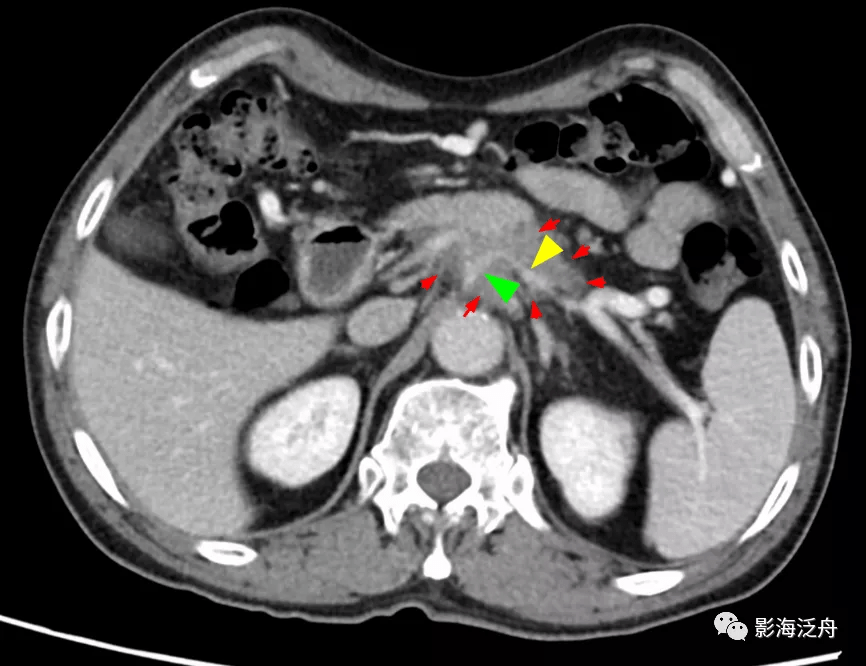

图中可见胰体部的弱强化肿块(红箭)包绕腹腔干(绿箭头)、脾动脉(黄箭头) 。